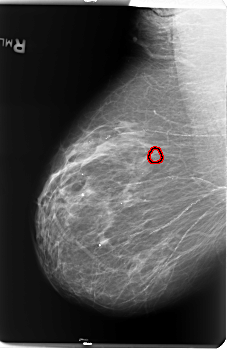

B_3141_1.RIGHT_MLO

RIGHT_MLO LINES 5936 PIXELS_PER_LINE 3848 BITS_PER_PIXEL 12 RESOLUTION 50 OVERLAY

FILE: B_3141_1.RIGHT_MLO.OVERLAY

TOTAL_ABNORMALITIES 1

ABNORMALITY 1

LESION_TYPE CALCIFICATION TYPE PLEOMORPHIC DISTRIBUTION CLUSTERED

ASSESSMENT 4

SUBTLETY 3

PATHOLOGY BENIGN

TOTAL_OUTLINES 1

BOUNDARY